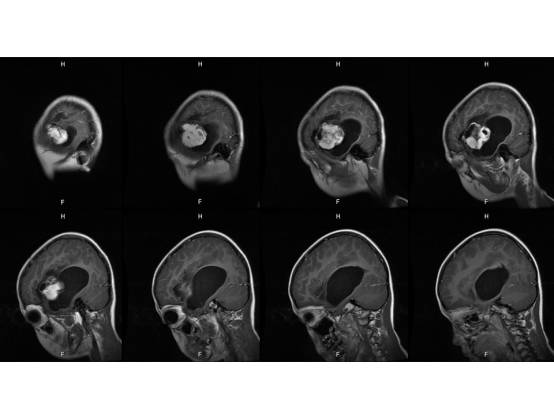

MR平扫及增强示:

MR

左侧颞叶见大块状等长T1等长T2异常信号,FLAIR呈高新,DWI(b=1000)实质部分呈稍高信号,ADC实质部分呈等信号,边界尚清,周围脑实质受压。注入GD-DTPA后病变实质部分呈明显强化。

结果7例肿瘤均位于颅内脑外,单发,体积较大,边界清楚,可见分叶,T1WI示肿瘤呈等信号或稍高信号,T2WI呈等信号或稍高信号,FLAIR呈稍高信号,DWI呈不均匀低信号,CT呈稍高密度影,增强扫描肿瘤实体性部分显著强化,内可见斑点、片状囊变或坏死区;4例可见脑膜尾征,肿瘤内及周边见血管流空或强化血管倍号; 瘤周水肿随肿瘤增大而明显;结论颅内血管周细胞瘤(HPC)是一种少见颅内脑外肿痫,肿痫形态不规则,边缘有分叶,增强扫描显著强化,内均可见斑点、片状囊变、坏死无强化区,瘤内无钙化,肿瘤周边可见血管流空信号,肿瘤恶变时,可见大片坏死出血,肿痛可侵犯破坏周围脑组织和骨组织,但无骨质增生。